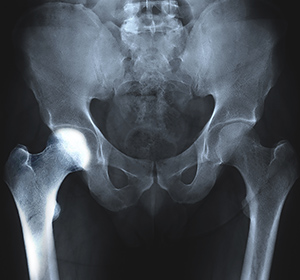

The hip joint is a ball-and-socket joint. A part of the pelvis bone known as the acetabulum forms the socket and the upper end of the femur, known as the femoral head, forms the ball.

You will also be recommended to undergo imaging studies such as X-rays, CT scans, MRIs, or nuclear scans to further document transient osteoporosis of your hip.